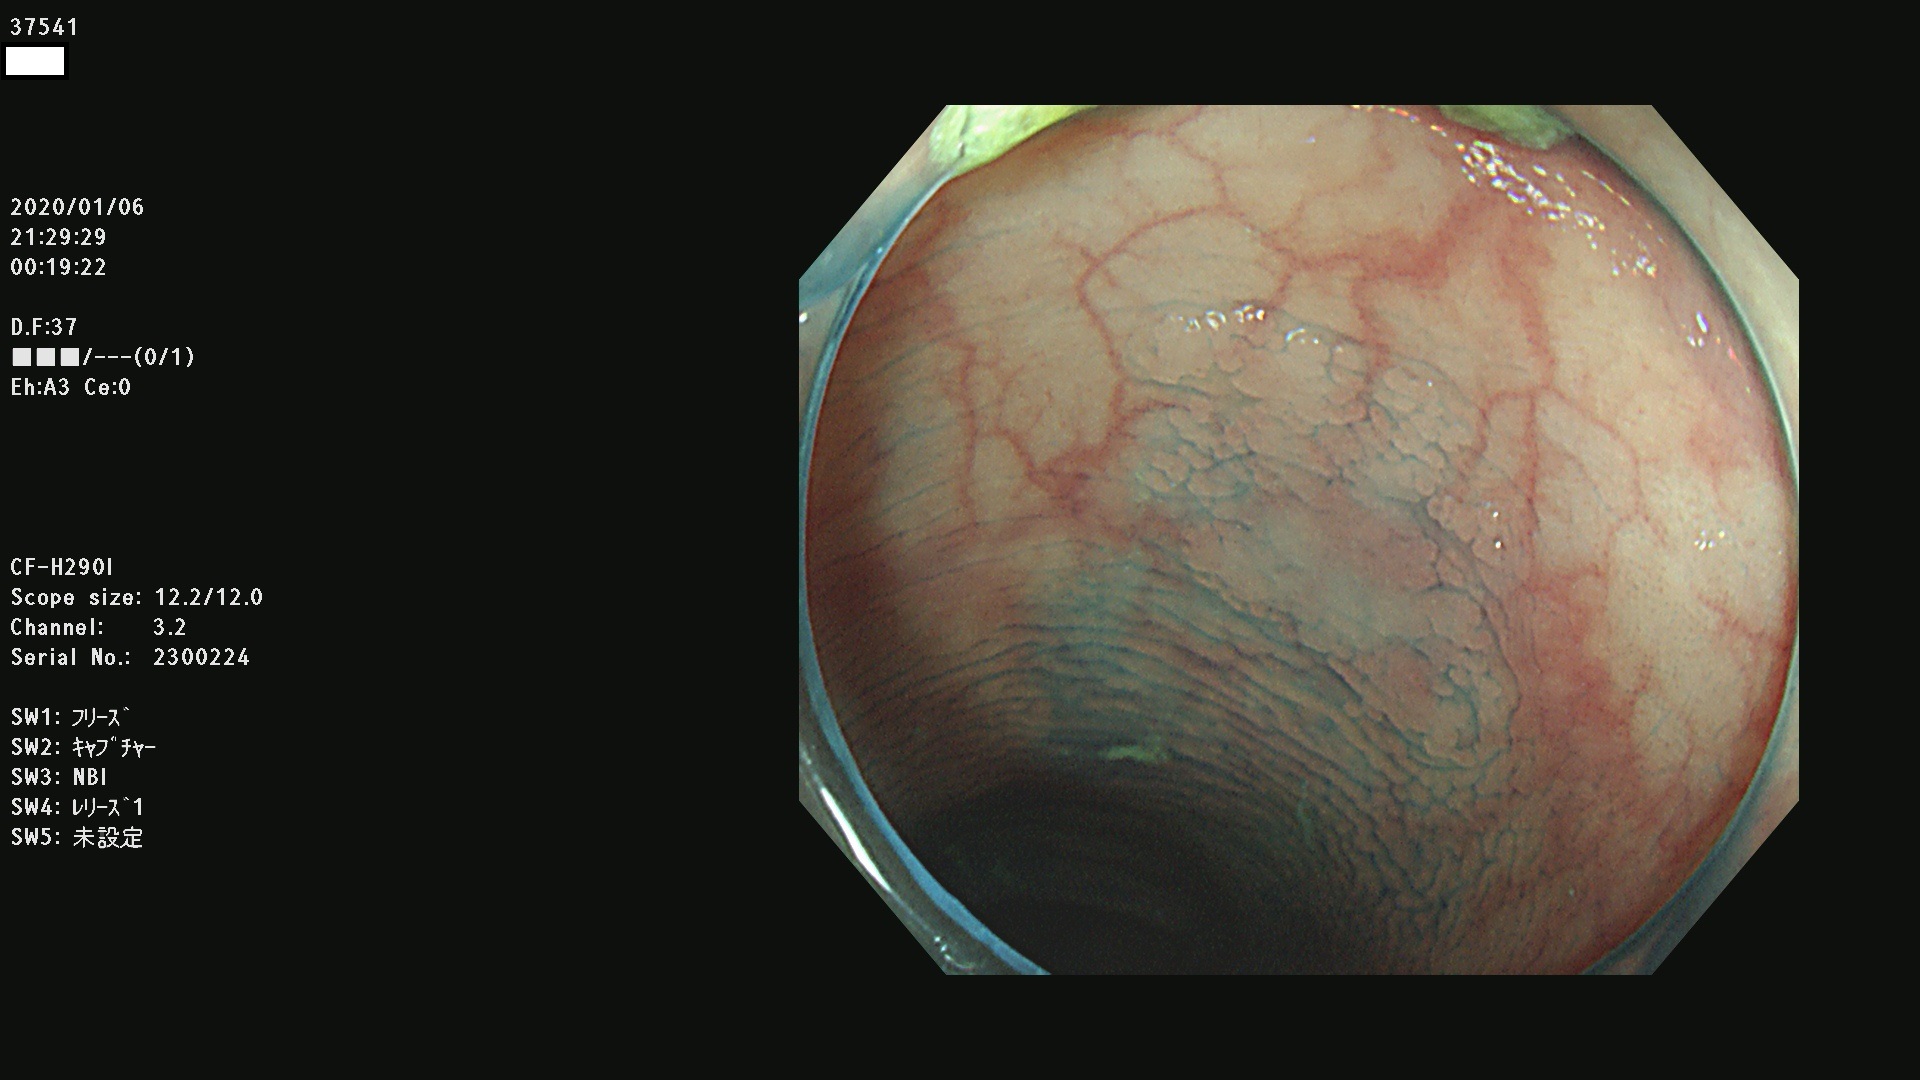

腺腫発見率 67 % (カルテ番号 37500〜37599の100名の方の検査結果で集計)大腸癌検診最新情報

以下のカルテ番号の方に腺腫(Adenoma,Group3〜5)が見つかりました(集計法)

37500 37502 37503 37505 37508 37509 37510 37511 37512 37513 37514 37517 37519 37520 37521 37525 37526(SSAPのみ) 37527 37528 37529 37531 37532 37533 37534 37536 37538(SSAPのみ) 37539 37541 37542 37543 37547 37548 37549(SSAPのみ) 37550 37552 37555 37556 37561 37562 37563(SSAPのみ) 37564 37565 37566 37567 37568 37570 37571 37572 37573 37574 37575(SSAPのみ) 37576 37577 37579 37580 37582 37583 37586(SSAPのみ) 37587 37588(SSAPのみ) 37590 37593(SSAPのみ) 37594 37596 37597(SSAPのみ) 37598 37599

発見困難で危険性の高い平坦型病変(上記100名より抽出) ![]()